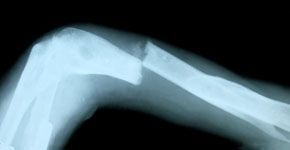

La dieta mediterránea reduce el riesgo de fracturas óseas, que sufrirán un tercio de mujeres y una quinta parte de los hombres, según conclusiones del XIV Congreso Nacional de la Asociación Española para el Estudio de la Menopausia (AEEM). Así lo demuestra un estudio publicado en la prestigiosa revista JAMA Internal Medicine del mes de mayo, en el que se demuestra que “una mayor adherencia a la dieta mediterránea está asociada a un menor riesgo de fracturas de cadera”. También es la conclusión de una investigación italiana publicada este mes de junio en Translational Medicine en la que comprobó una mayor densidad ósea entre quienes seguían la dieta mediterránea.

Una de las causas de la falta de adherencia al tratamiento es que “consiste en una enfermedad que no duele, que no da síntomas hasta que está avanzada”, señala. El doctor Díez-Pérez propone considerar el tratamiento de la osteoporosis como el de otras enfermedades crónicas como la hipercolesterolemia o la hipertensión, cuyo objetivo es acercarse a la normalidad. En el caso de la osteoporosis la finalidad es una densidad ósea normal, no desviada más de dos puntos negativos en la escala estándar de medición (T) con respecto a la población sana de la misma edad.

Otro de los fármacos en investigación que podría estar aprobado este año por la FDA, el organismo encargado de la autorización de medicamentos en Estados Unidos, añade, es un inhibidor de la esclerostina, una sustancia que sólo produce el osteocito, con lo que “estimularía la acción del osteoblasto, lo que no ocurre con los tratamientos actuales”. Sus resultados en fase 3 son una reducción de fracturas de cadera de casi la mitad (47-48%).